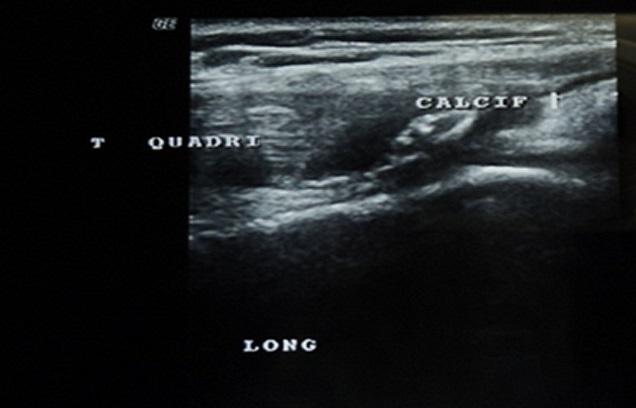

Spontaneous ruptures of the quadriceps tendon are infrequent injuries, it is seen primarily in patients with predisposing diseases such as gout, rheumatoid arthritis and chronic renal failure. A 32-year-old man had a history of end stage renal disease and received regular hemodialysis treatment for more than 5 years. He was admitted in our service for total functional impotence of the right lower limb with knee pain after a common fall two months ago. The radiogram showed a ''patella baja" with suprapatellar calcifications. The ultrasound and MRI showed an aspect of rupture of the quadriceps tendon in its proximal end with retraction of 3 cm. Quadriceps tendon repair was performed with a lengthening plasty, and the result was satisfactory after a serial rehabilitation program. The diagnosis of quadriceps tendon ruptures needs more attention in patients with predisposing diseases. They should not be unknown because the treatment of neglected lesions is more difficult. We insist on the early surgical repair associated with early rehabilitation that can guarantee recovery of good active extension.

股四头肌肌腱自发性断裂是一种罕见的损伤,主要见于患有痛风、类风湿性关节炎和慢性肾衰竭等易感疾病的患者。一名32岁男性有终末期肾病病史,接受规律血液透析治疗超过5年。两个月前他因一次普通跌倒后出现右下肢完全功能性阳痿伴膝关节疼痛而入住我院。X线片显示“低位髌骨”伴髌上钙化。超声和磁共振成像显示股四头肌肌腱近端有断裂迹象,回缩3厘米。采用延长成形术进行股四头肌肌腱修复,经过一系列康复计划后效果满意。对于患有易感疾病的患者,股四头肌肌腱断裂的诊断需要更多关注。不应忽视此类情况,因为治疗被忽视的损伤更加困难。我们坚持早期手术修复并结合早期康复,这可以保证良好的主动伸展恢复。